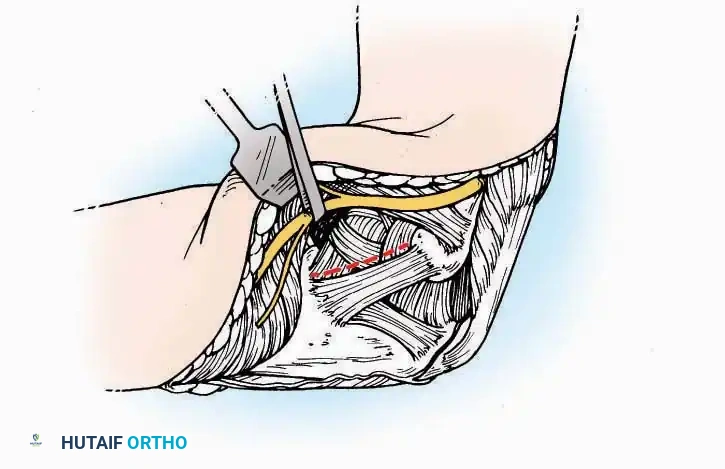

Lateral Approach (Extensile Lateral)

This is the workhorse approach for open reduction and internal fixation (ORIF) of displaced intra-articular calcaneal fractures.

Indications: ORIF of calcaneus fractures, lateral wall exostectomy, subtalar arthrodesis.

Positioning: Lateral decubitus with the operative leg up, or supine with a large bump under the ipsilateral hip to internally rotate the leg.

Surgical Technique:

* Incision: Begin the incision on the lateral margin of the Achilles tendon near its insertion. Extend it distally to a point 4 cm inferior and 2.5 cm anterior to the lateral malleolus. (For trauma, a classic L-shaped extensile incision is often used, dropping straight down anterior to the Achilles, then curving gently toward the base of the 5th metatarsal).

* Superficial Dissection: Divide the superficial and deep fasciae. It is imperative to create a "full-thickness" flap containing skin, subcutaneous fat, and periosteum to prevent flap necrosis.

* Nerve Protection: The sural nerve crosses the proximal and distal limbs of this approach. It must be identified and protected within the anterior flap.

* Deep Dissection: Isolate the peroneal tendons (longus and brevis). Incise and elevate the periosteum below the tendons to expose the lateral wall of the calcaneus.

* Tendon Management: If severe deformity or infection is present, the peroneal tendons may be divided via Z-plasty and repaired at the conclusion of the case, though this is rarely necessary in modern fracture care.